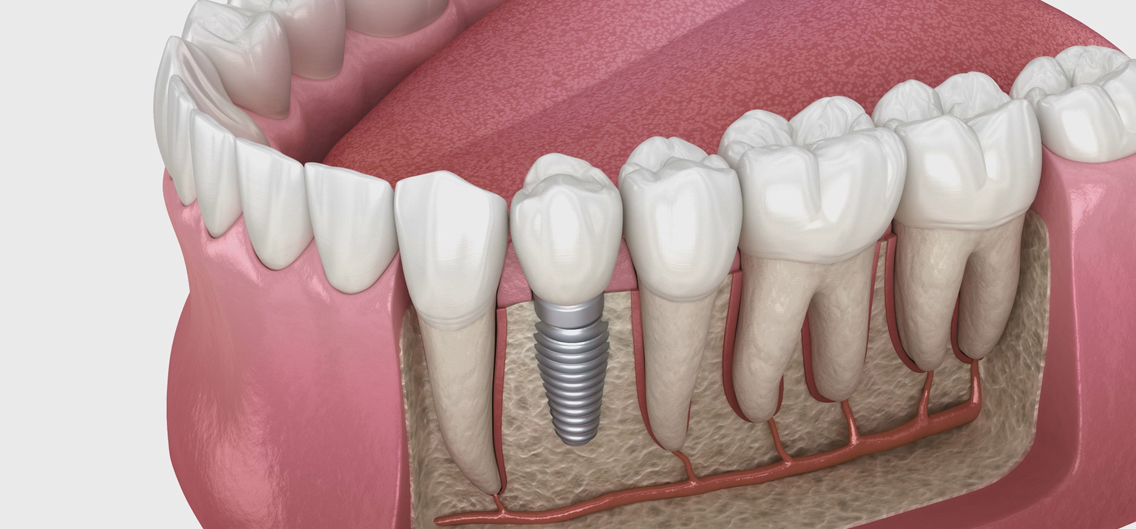

치조골에 임플란트 픽스처(뿌리 역할)를 정확하게 심는 단계로, 국소마취 하에 안전하게 진행됩니다.

임플란트와 턱뼈가 자연스럽게 결합되는 기간입니다. 이 과정은 안정적인 고정력을 형성하는 데 매우 중요합니다.